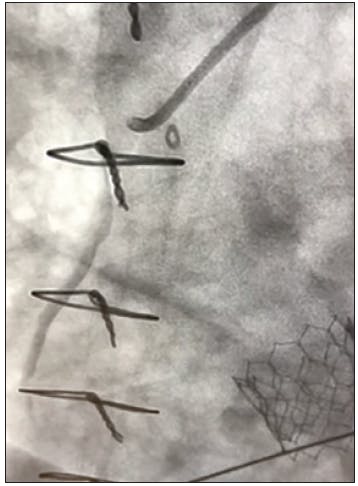

Prior to the procedure, ticagrelor was administered and the patient was taken to the cardiac cath lab for angiography. The initial angiogram revealed TIMI 0 flow in the proximal right coronary artery (RCA) due to plaque rupture. The patient received a 3.5- X 38-mm everolimus-eluting stent (Synergy™ drug-eluting stent [DES], Boston Scientific Corporation) with postdilation optimized by intravascular ultrasound (IVUS) and was then sent to the step-down unit. The patient vomited the ticagrelor within 2 hours of administration and cangrelor was started. Due to continual vomiting, an electrocardiogram was obtained that showed an acute MI. The patient was brought back to the cardiac cath lab for follow-up angiography that revealed TIMI 0 flow of the RCA (Figure 1).

INTERVENTION

Manual aspiration using a Pronto V3 (Teleflex) catheter restored some flow, however, distal embolization to the posterior descending artery (PDA) immediately caused right ventricular cardiac arrest (Figure 2). The patient underwent six shocks and was intubated while CAT RX was delivered through the freshly placed 3.5- X 38-mm DES to the PDA. Two passes of CAT RX with the Penumbra ENGINE resulted in TIMI 3 flow restoration and retrieval of the distal emboli from the PDA (Figure 3). The patient’s symptoms normalized, the electrocardiogram stabilized, and the acute MI was immediately resolved. The patient remained on cangrelor with no need for tirofiban.